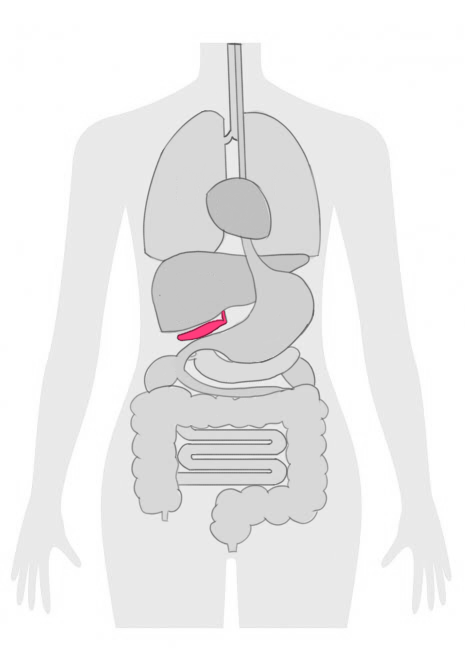

胆嚢がんは、胆嚢の内側の粘膜から発生するがんの一つです。

胆嚢がんのリスク因子には、胆石症や慢性の胆嚢炎、家族歴などがあります。

定期的な健診や超音波検査を受けることで、早期に胆嚢がんを発見することが可能となります。